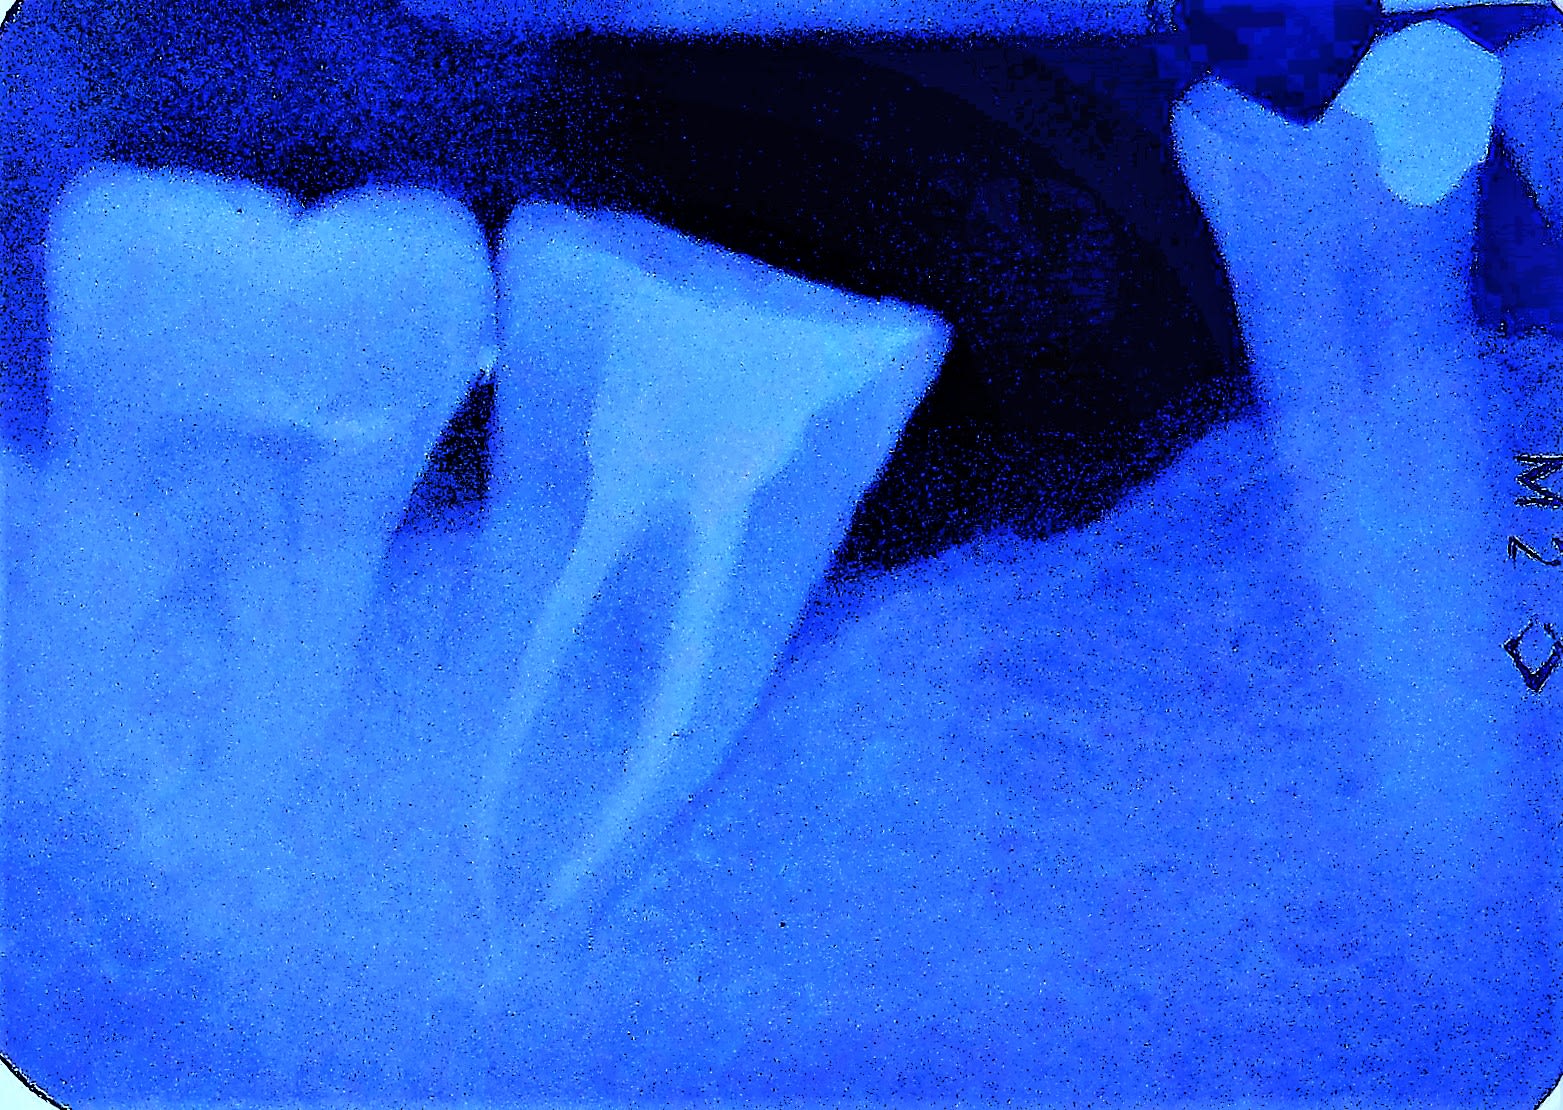

Hier soir.... tentative de retraitement sur une 15.... initialement traitée en 2000.

CIC sur i core, fistule vestibulaire à mi hauteur de la racine, pas pu en suivre le cheminement.

Soit souci apical soit félure...

J'avais déposé la coiffe et l' i core vers le 8 mars, commencé la desobturation et laissé de la girofle en interseance sous l'ic rescellé provisoire.

Hier: fistule disparue, pas de sensibilité, plutot content mais supicieux car j'avais pas atteint les apex....

J'ai continué à nettoyer les racines et obturé comme j'ai pu sans arriver à passer l'apex, moins content.

On va sans doute refaire un i core si la dent reste asymptomatique histoire de bien sceller les racines et attendre quelques mois avec une provisoire par dessus parceque du coup vu que j'ai pas atteint l'apex mais fait disparaitre la fistule je subodore un loup genre félure....

Je finis l'endo, rescelle mon ic et refais un provisoire et je vais voir la 36.... ras sur l'implant par contre voussure gencive vestibulaire de 35, sondage et ça descend le long de la racine..... sans doute félée ou fendue....